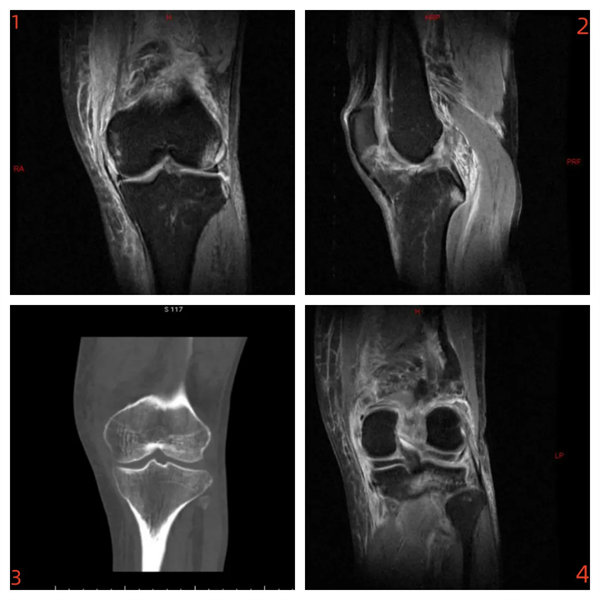

術前影像:

內側副韌帶斷裂(圖1)、前交叉韌帶斷裂(圖2)、脛骨平臺外側緣骨折(圖3)、內、外側半月板II-III°損傷(圖4)